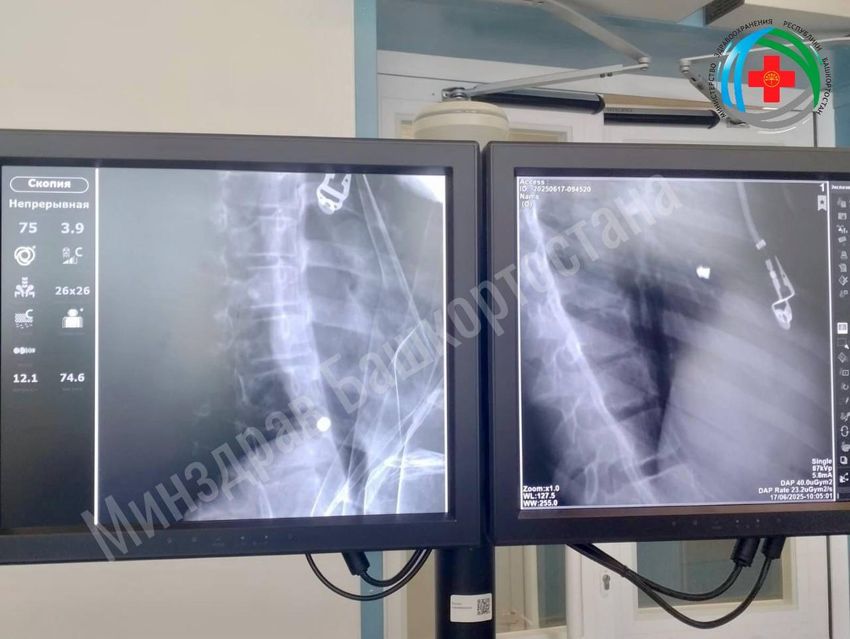

Хирурги провели операцию, в ходе которой вытащили пробившую сердце и легкое пулю. Пока что девочка лежит в кардиоцентре, но быстро идет на поправку.